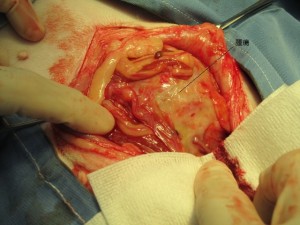

術中の様子です。

腹腔内をほぼ腫瘍が占めていました。

同時に血液が1L近くたまっていました。